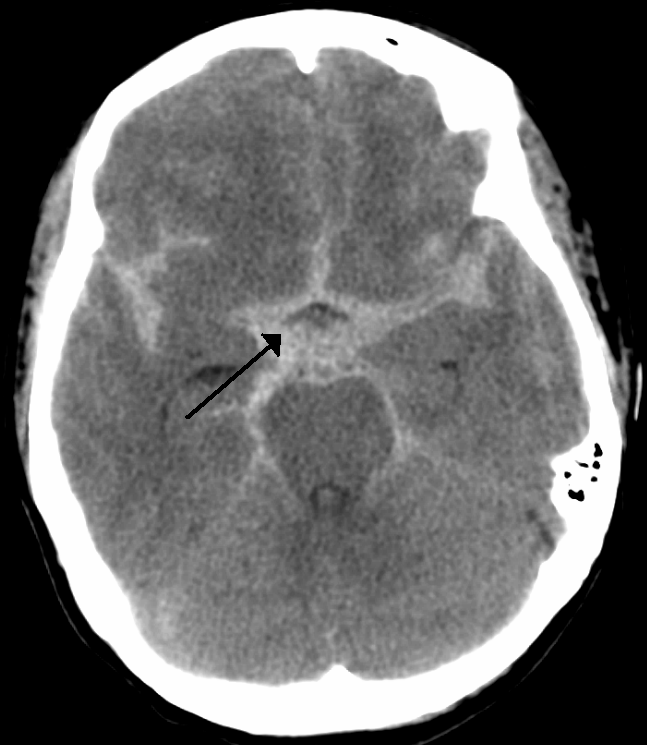

A 65 yo F presents to the ED with a complaint of headache. The patient is brought in by her husband. The patient states the headache is a 10/10 and started while she was carrying laundry up the stairs. The patient has a history of migraines, but this headache is ‘much worse and feels different’. She has vomited twice since the start of the headache and continues to be nauseated. She also has light and noise sensitivity. The patient also feels lightheaded and like she might ‘pass out’.

Most like subarachnoid hemorrhage

●CT scan of brain (non-contrast)

acute extravasation of blood into the space between the arachnoid membrane and the pia mater.